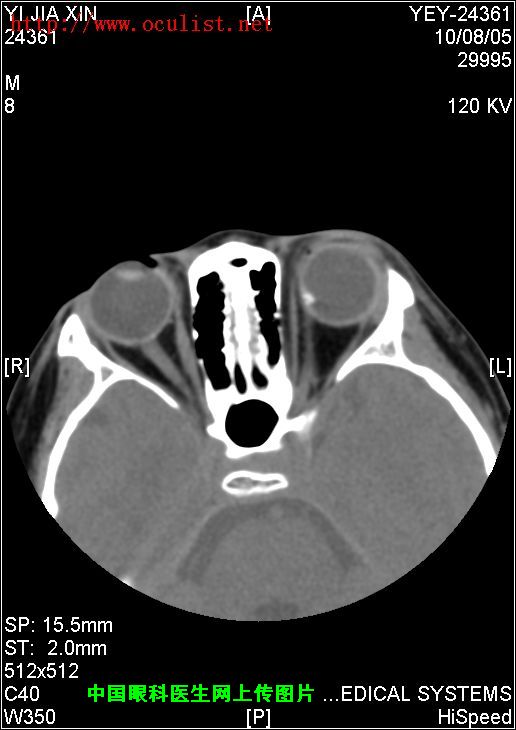

[组图]患者男,9岁,发现左眼外斜9年         ★★★

患者男,9岁,发现左眼外斜9年

患者男,9岁,发现左眼外斜9年,检查:左眼视力0.01(矫正不应),左眼外斜400,角膜、晶状体未见异常,眼底如下图,CT如下图,RMI暂无,请分析一下该患儿的诊断?

眼底图和CT片: